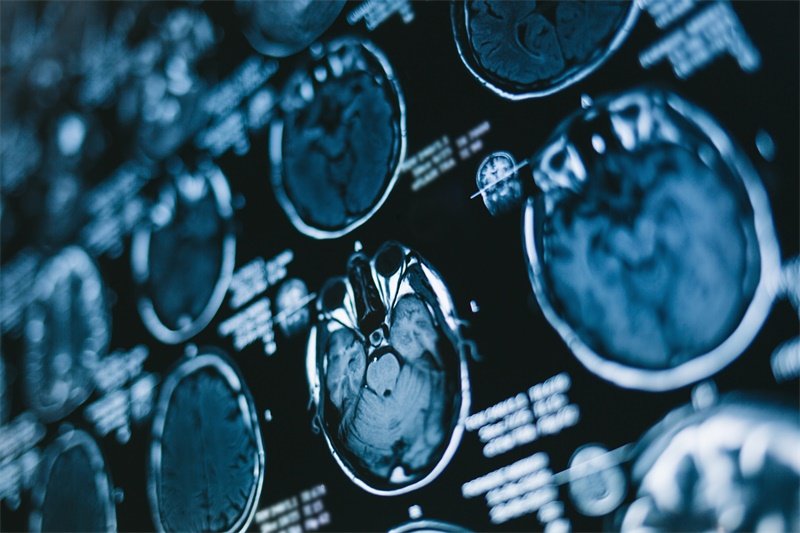

在医学成像中,蝶骨嵴区的清晰度也反映了这一区域的健康状态。如果边界不清,可能意味着区域内有潜在的病变或者其他问题。

占位边界欠清是医学影像学中常用的一个术语,它描述了某一特定区域在影像上呈现出模糊不清的边界。这种现象在蝶骨嵴区尤其值得关注,因为它可能指向多种病理状态。

通常,影像学中看到的占位边界欠清可能是由肿瘤、囊肿、感染或其他病变造成的。它不仅仅是影像结果的描述,也可能对患者的治疗和管理产生重要影响。

如果存在肿瘤风险,医生可能会建议进一步的检查,比如MRI或CT扫描,以便更全面评估病变情况。此外,必要时可以安排组织活检以明确诊断。